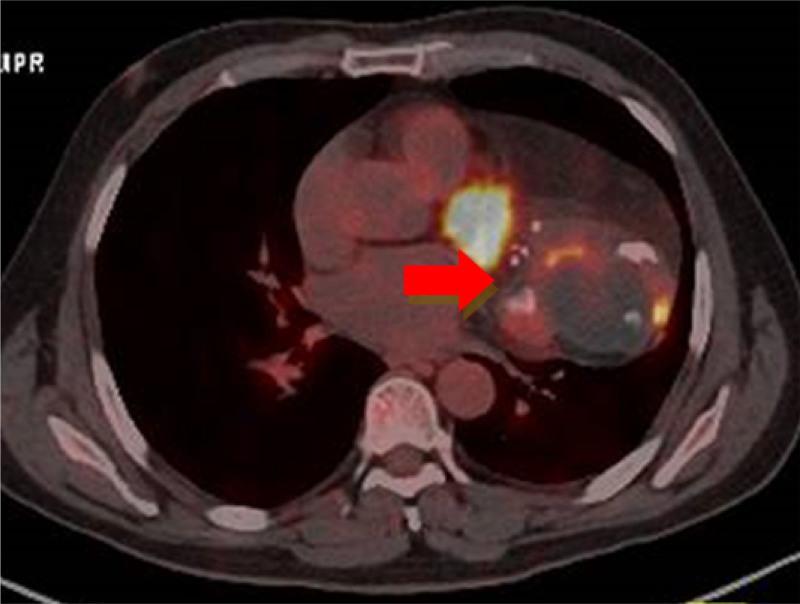

A 51-year-old man was admitted with cough and sputum accompanied by fever. X-ray and CT showed a bulky anterior mediastinal mass that was initially misdiagnosed as a teratoma. PET/CT demonstrated a lesion on that location showing a small area of moderately intense uptake. After surgical excision, histopathological examination via hematoxylin and eosin first revealed the diagnosis of malignant undifferentiated tumors. The results of immunohistochemical evaluations were as follows: P63 (scattered +), VIMENTIN (giant cell +), CD68 (KPI; giant cell +), SMA (-), and Ki-67 (Li: 50%). Molecular pathology: MDM2 gene status (+) with amplification.

一名51岁男性因咳嗽、咳痰伴发热入院。X线和CT显示前纵隔有一个巨大肿块,最初被误诊为畸胎瘤。PET/CT显示该部位有一个病变,有一小片区域摄取中等强度放射性。手术切除后,苏木精-伊红染色的组织病理学检查最初显示为恶性未分化肿瘤。免疫组化评估结果如下:P63(散在阳性)、波形蛋白(巨细胞阳性)、CD68(KPI;巨细胞阳性)、平滑肌肌动蛋白(阴性)和Ki-67(Li:50%)。分子病理学:MDM2基因状态为阳性且有扩增。